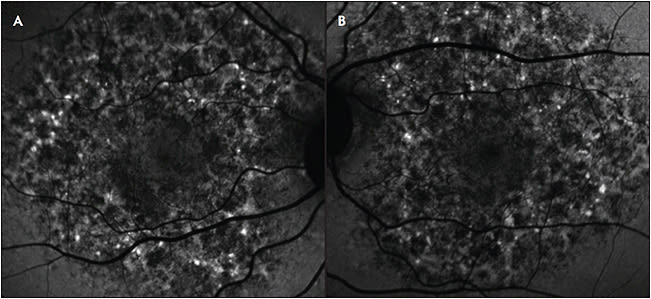

In 2018, a pigmentary maculopathy was described in the setting of chronic exposure to the drug pentosan polysulfate sodium (PPS), which is used in the treatment of interstitial cystitis. Visual acuity appeared to be preserved initially, with patients reporting difficulty reading and prolonged dark adaptation.13,14 This toxic maculopathy has been thought to progress after discontinuation of PPS (Figure 2).15 On fundus examination, there are often subtle hyperpigmented macular spots with interspersed pale yellow deposits. Fundus autofluorescence images may demonstrate large confluent areas of mottled increased and decreased AF spots, in most cases involving the fovea.16 Spectral-domain OCT shows elevation and thickening of the RPE. These RPE findings have been noted to be dynamic over time.16 Some reports have demonstrated more widespread changes correlating to the cumulative dose of PPS, with attempts to quantify the imaging changes.17 With increased awareness of this likely drug toxicity, we can expect to continue to learn more about the natural history, risk factors, and management of this condition. Recent data have led some urologists to question the role of PPS in treating interstitial cystitis: a randomized, double-blind controlled trial showed no benefit of the drug over placebo in controlling symptoms of interstitial cystitis.18